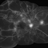

- peripheral ischemia

- Imaging device

- Fundus camera

- Peripheral ischemia by angiography with montage